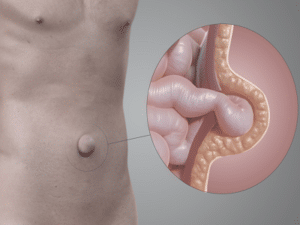

La hernia en el ombligo ocurre cuando una parte del contenido abdominal se desplaza a través de una zona débil alrededor del anillo umbilical y